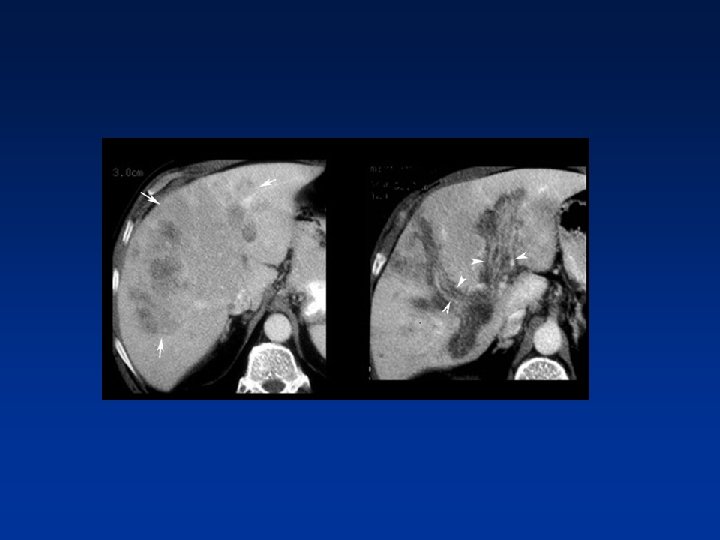

HCC & PV thrombosis Many patients with cirrhosis have portal venous thrombosis and many patients with HCC have thrombosis. These are two common findings and they can be coincidental. It is very important to make the distinction between just thrombus and tumor thrombus. First, if you have a malignant thrombus in the portal vein, it will always enhance and you'll see it best in arterial phase. Secondly, if you have a malignant thrombus in the portal vein, it will increase the diameter of the vessel. Sometimes a tumor thrombus may present with neovascularity within the thrombus.

• Above : diffusely enhancing tumor thrombus in HCC with portal venous thrombosis. • Down: tumor thrombus with vessels within the thrombus